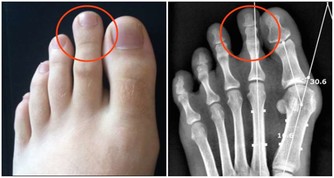

口腔潰瘍的情況下密切接吻有可能感染艾滋病。

3.口腔有潰瘍出血。

因此,口腔潰瘍出血在概率上的確存在感染的可能,但被感染的機率微乎其微。

至於很多人擔心,有口腔潰瘍的情況下接吻感染,就​​算真的發生,也是因為血液暴露,歸於血液傳播,而不能說接吻是艾滋病的一個傳播途徑。